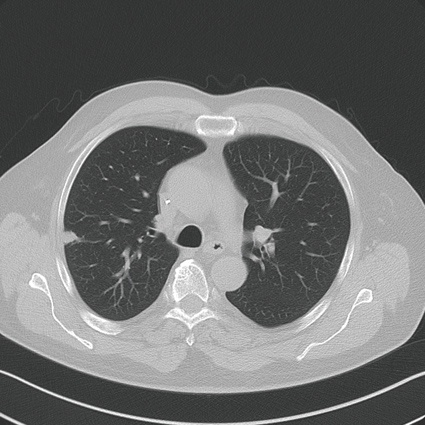

- Optimierte lokale Therapiekontrolle: Vollständige Ablation (A0-Ablation)

Zielsetzung der Mikrowellenablation (und weiteren Ablationstechniken) ist die komplette Destruktion aller vitalen Tumorzellen im Zielvolumen mit einem Sicherheitssaum, Minimierung der Schädigung von Umgebungsstrukturen. Die möglichen Vorteile gegenüber einem chirurgischen Verfahren liegen in der hohen Ortspräzision und dem selektiven Zugangsweg und einer minimal-invasiven Behandlungsstrategie mit tagesstationärer Durchführbarkeit und einer geringeren Belastung des umgebenden normalen Lungenparenchyms. Die Grundlage der Therapie ist dabei die Erzielung einer Temperaturerhöhung intratumoral und in den Sicherheitszonen zwischen 80 und 100 Grad Celsius und geht in der Regel einher mit einer kompletten Destruktion von Zellanteilen wie den Mitrochondrien im Zytoplasma und weiteren Leitstrukturen.

Zusammenfassend stellt die Mikrowellenablation von primären Lungentumoren (NSCLC) und Lungenmetastasen eine vielversprechende neue Therapietechnik dar bei hoher Effizienz und guten lokalen Ortskontrolldaten im Vergleich zu den bisherigen Verfahren der Radiofrequenzablation und der laserinduzierten Thermotherapie. Insbesondere die Lage eines Herdes und die Größe vor der Ablation bestimmen dabei die lokalen Tumorkontrollergebnisse. Eine Tumorgröße von mehr als 3 cm erweist sich für die thermische Ablation als problematisch. Weitere prospektive Arbeiten müssen sich mit dem Thema der Thermoablation und Korrelation zu chirurgischen Strategien, aber auch anderen Ablationsverfahren auseinandersetzen.